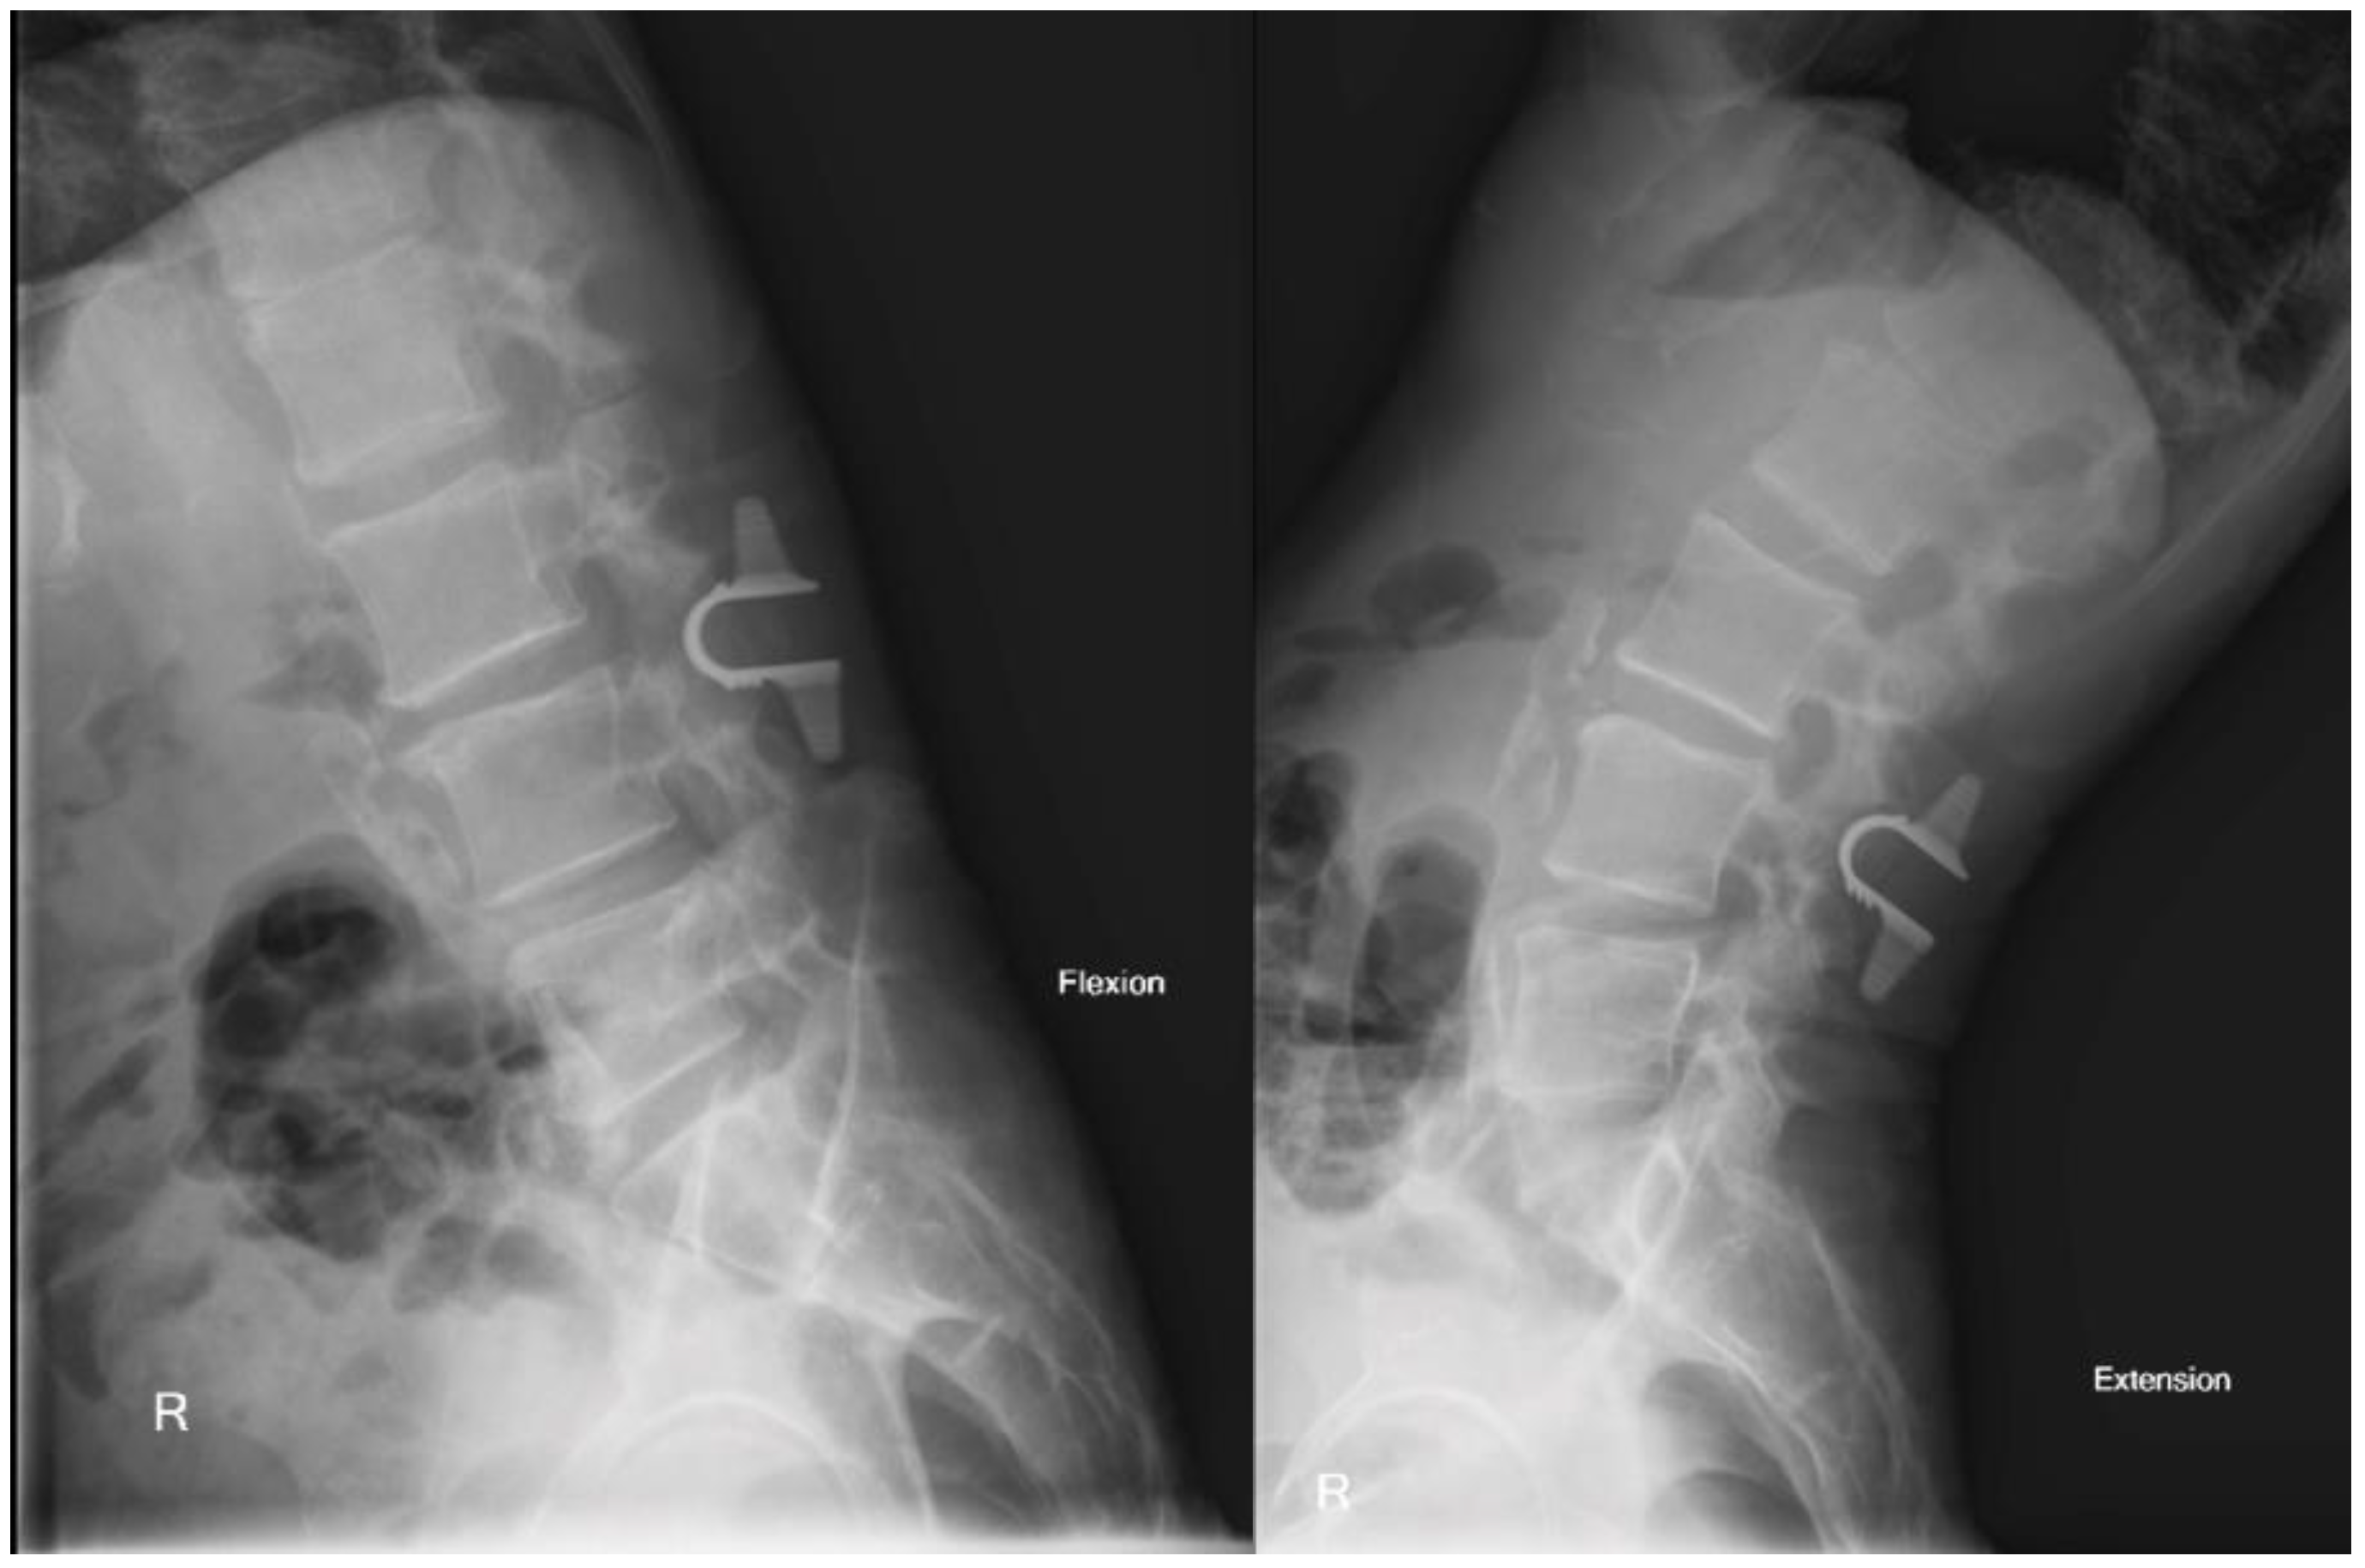

The patient’s postoperative hospital stay was undemanding as well, and he was discharged home on postoperative day 1. He subsequently completed follow up clinic appointments through 2 years with self-reported resolution of symptoms. Post-operative films display successful hardware placement without post-operative instability (Figure 5).

Figure 5. Postoperative flexion and extension X-ray at 1 year follow up showing effective hardware placement without iatrogenic instability.